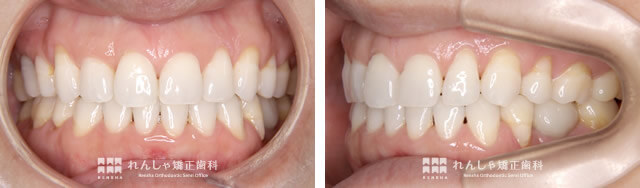

矯正治療を終えて

治療を終えた後も、C.Nさんにはリテーナーで歯並びの維持をつづけてもらっています

治療を進める上で、左下奥歯を抜歯せざるをえなくなったC.Nさん。抜歯した部分には、歯科インプラント治療を受けていただくことに。

C.Nさんは、すでに治療後8年が経過していますが、毎日ではないもののリテーナーの装着を続けてもらっています。

リテーナーの装着を面倒に思われる方もいらっしゃいますが、歯並びを長く維持するには大事な事。聞けばCNさんは、リテーナーが習慣になっていらっしゃるとのこと。実際、歯並びもしっかり維持できています。

治療前は口元のことで人の目が気になっていたと話されていたC.Nさん。矯正治療は噛み合わせの改善も当然大事ですが、心理面での好影響も期待できます。